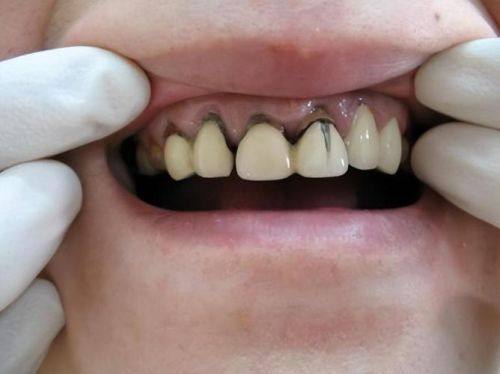

3. 口腔修复:针对牙齿缺损、缺失等问题,提供专精的修复方案,使牙齿修复正常功能和外观。

1. 李贞:主治医师,擅长正畸口腔修复、前瓷牙美容修复,拥有10多年的从业经验,技术不错,能为患者提供个性化的治疗方案。

7. 烤瓷牙:800 - 3000元